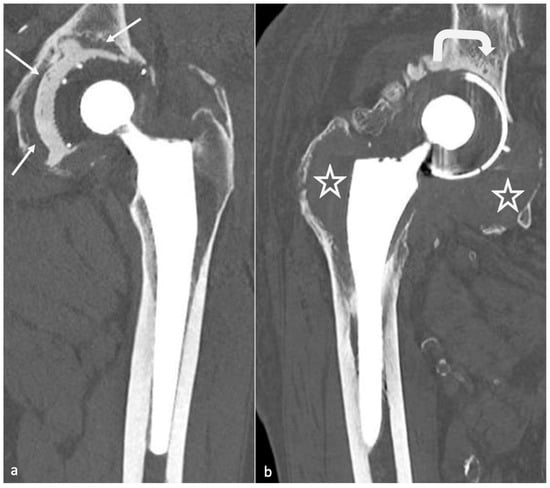

- Metallosis results from the shedding of metallic debris (secondary to a MoM prosthesis with corrosion, a conflict between a metallic acetabular cup and the prosthetic neck, or a contact between a metallic head and an acetabular metal back in case of PE wear or dislocation) that induces synovitis and an indolent pattern of osteolysis, potentially leading to loosening (i.e., potentially looking similar to osteolysis and PE wear). Synovitis may contain low-signal intensity or metallic density debris, causing MRI artifacts and bone erosion, best depicted on CT-MAR (Figure 20). Such debris might also be located in periprosthetic soft tissue and lymph nodes [54,57]. Metallic debris presence might also accentuate PE wear (i.e., third fragment wear) [54]. Of note, high serum metal-ion levels can be found in symptomatic and asymptomatic patients and would be associated with pseudo-tumors, so that such a biological finding should lead to the prescription of an MRI to rule out a pseudo-tumor even in asymptomatic patients [6,103].

- Additionally, referred to as trunnionosis, trunnion corrosion corresponds to a soft-tissue reaction to metal debris released from micromotion and mechanical wear at the head–neck or neck–stem junction of modular MoP HA. On MRI, it manifests as an adverse local reaction associated with medial calcar resorption [11,104].